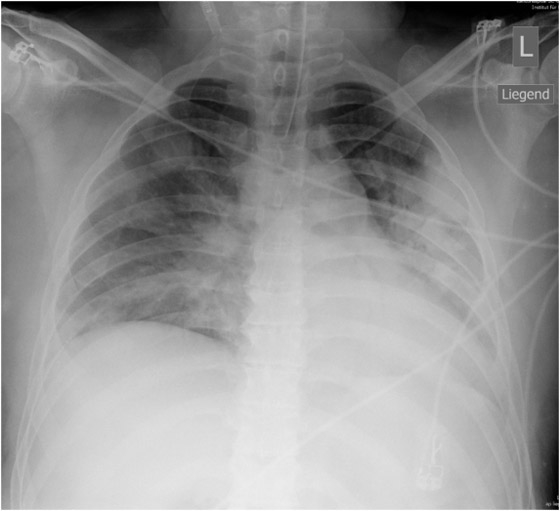

Figure 1

X-ray course of patient A. Left, normal chest x-ray (p.a., erect) at admission. Center, chest x-ray (p.a., supine) on day 4, showing massive infiltration. Right, chest x-ray (p.a., supine) day 14, after 10 days on oseltamivir and 5 days on steroids, showing regression of infiltration.

Patient A (male, 41 years), with OSAS, was hospitalised for fever and general symptoms with proven A/H1N1v infection. At that time he had leukocytosis (13 g/L), lymphopenia (11%) and a CRP count of 113 g/L, but his lung tests and chest x-ray remained normal (fig. 1a). Four days later the patient rapidly developed respiratory insufficiency requiring intubation. At this time bilateral coarse rales were heard on pulmonary auscultation and the chest x-ray showed diffuse bilateral pulmonary infiltrates (fig. 1b). Oseltamivir was started only then. The disease course was highly complicated with the longest duration of hospitalisation in this series (36 days, including 19 days in intensive care, 13 days intubated). Figure 1c shows slow recovery on day 14 after 10 days of oseltamivir and 5 days of steroids. Recovery was further complicated by generalised weakness requiring admission to a rehabilitation unit.